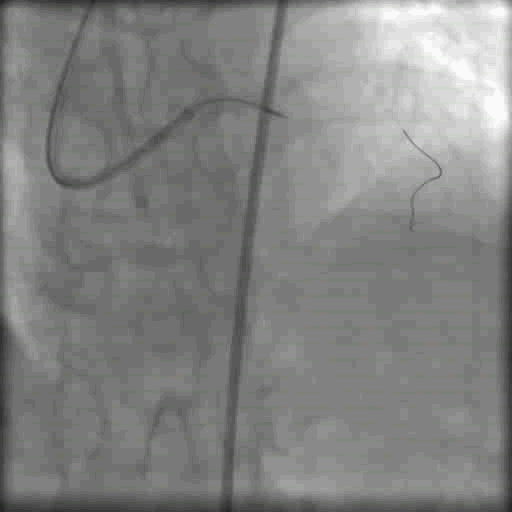

双侧造影

双侧造影显示闭塞段不长,右冠向左冠发出侧支循环供血,但是LAD闭塞段开口仍不清晰

通过双侧造影判断LAD 大致走形方向(图中箭头所示)